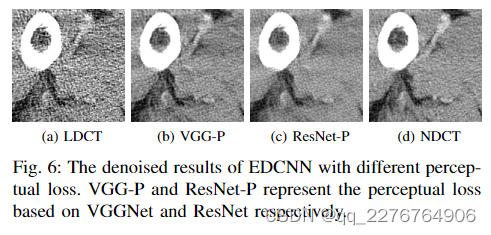

2)感知损失模型:如第 III-C 节所示,在我们的方法中选择用于计算感知损失的模型是 ResNet-50。 关于感知损失的模型,我们将ResNet-50与现有方法常用的VGGNet-19进行比较。 在本实验中,我们仅通过单一感知损失来训练 EDCNN 模型。 根据之前的方法,我们使用VGGNet-19最后一个卷积层的输出来计算损失。 对于我们使用的ResNet-50,我们同样利用其最后一个卷积层的特征图进行比较。

通过感知损失优化的模型往往会输出带有某种类似纹理的噪声的图像。 仔细观察图6,我们可以发现图6b的噪声颗粒度比图6c的噪声颗粒度大。 并且从视觉外观来看,图6c更接近NDCT图像(图6d)。 因此我们在感知损失函数中使用ResNet-50模型,它比VGGNet具有更强的特征提取能力。